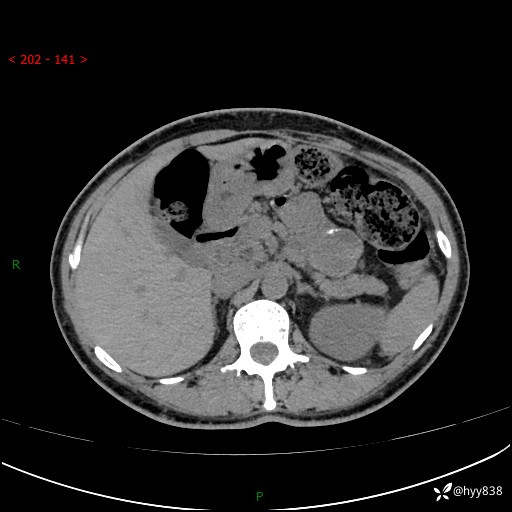

胰腺CT平扫

img